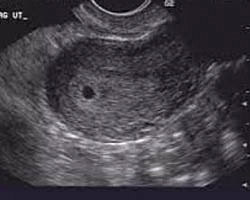

• semana 1

semana 1

al cabo de una semana de la relación sexual, se lleva a acabo la implantación del ovocito secundario.